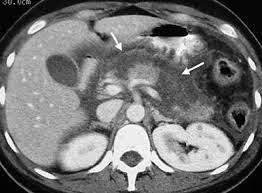

Απεικονιστικές εξετάσεις

- Αξονική τομογραφία

Επίσης, το επίπεδο της CRP και τα ευρήματα από την αξονική τομογραφία έχουν προγνωστική αξία.